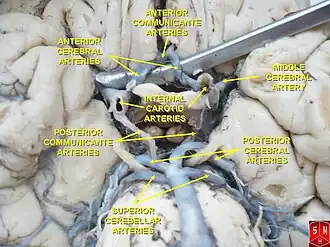

The arteries of the base of the brain. Basilar artery labeled below center. The temporal pole of the cerebrum and the cerebellar hemisphere have been removed on the right side. Inferior aspect (viewed from below). | |

The circle of Willis is a part of the cerebral circulation and is composed of the following arteries:[3]

- Anterior cerebral artery (left and right) at their A1 segments

- Anterior communicating artery

- Internal carotid artery (left and right) at its distal tip (carotid terminus)

- Posterior cerebral artery (left and right) at their P1 segments

- Posterior communicating artery (left and right)

The middle cerebral arteries, supplying the brain, are also considered part of the Circle of Willis [4]

The left and right internal carotid arteries arise from the left and right common carotid arteries.

The posterior communicating artery is given off as a branch of the internal carotid artery just before it divides into its terminal branches - the anterior and middle cerebral arteries. The anterior cerebral artery forms the anterolateral portion of the circle of Willis, while the middle cerebral artery does not contribute to the circle.

The right and left posterior cerebral arteries arise from the basilar artery, which is formed by the left and right vertebral arteries. The vertebral arteries arise from the subclavian arteries.

The anterior communicating artery connects the two anterior cerebral arteries and could be said to arise from either the left or right side.